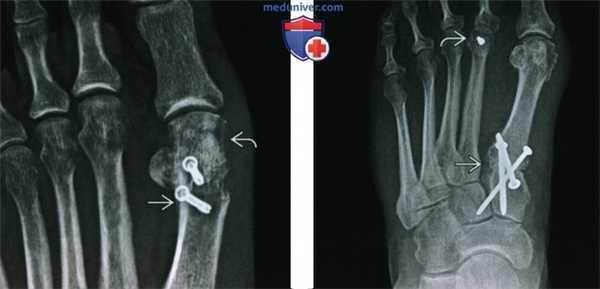

(Слева) Рентгенография в ПЗ проекции: бурсэктомия и шевронная остеотомия с боковым смещением головки первой плюсневой кости через участок остеотомии. Шевронная остеотомия нечетко визуализируется при ПЗ рентгенографии, так как имеет V-образную форму в сагиттальном сечении.

(Справа) Рентгенография в ПЗ проекции: остеотомия первой плюсневой кости в сочетании с артродезом предплюсне-плюсневого сустава, выполненная для коррекции гиперподвижности первого пальца стопы и варусной деформации первой плюсневой кости. Укорачивающая остеотомия головки второй плюсневой кости была также выполнена для коррекции деформации стопы Мортона.

(Справа) Рентгенография в ПЗ проекции, тот же пациент после остеотомии первой проксимальной фаланги и первой кости плюсны: теперь определяется ятрогенное укорочение первого пальца, что может привести к механической метатарзалгии. (Слева) Рентгенография в ПЗ проекции: бурсэктомия и шевронная остеотомия с боковым смещением головки первой плюсневой кости через участок остеотомии. Шевронная остеотомия нечетко визуализируется при ПЗ рентгенографии, так как имеет V-образную форму в сагиттальном сечении.